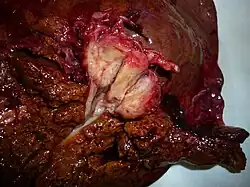

Guz Klatskina, preparat po hemihepatektomii

Guz Klatskinarak dróg żółciowych (łac. cholangiocarcinoma) o charakterystycznej lokalizacji w okolicy wnęki wątroby.

Guzy o tej lokalizacji stanowią ⅓ wszystkich gruczolakoraków, występują najczęściej u starszych mężczyzn i wiążą się ze znaczną śmiertelnością - jedynie około 10% pacjentów udaje się wyleczyć.